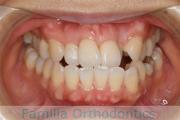

No.21V-424

- 主な症状:

- 上顎前突

- その他の症状:

- 叢生

- 年齢:

- 23歳

- 性別:

- 女性

- 抜歯部位

- 上:

- 44

- 下:

- 8|2

- 主な使用装置:

- FEA 022

- 治療にかかった費用:

- 90万円

でこぼこと八重歯が気になるとのことで来院されました。上下のあごのズレ(下顎の後退)が相当に強かったため、下は左右から小臼歯を抜歯する代わりに下の前歯を一本だけ抜歯する治療方針を採用させていただきました。

下顎の後退は呼吸機能にも影響しますので、ある一定上のズレがある方は、下あごの前方移動術のオペも検討します。こちらの方は、そこまでリスクが高いとは判断しませんでした。

- ≫治療前

-

上顎

下顎

前歯の関係など

右側

正面

左側